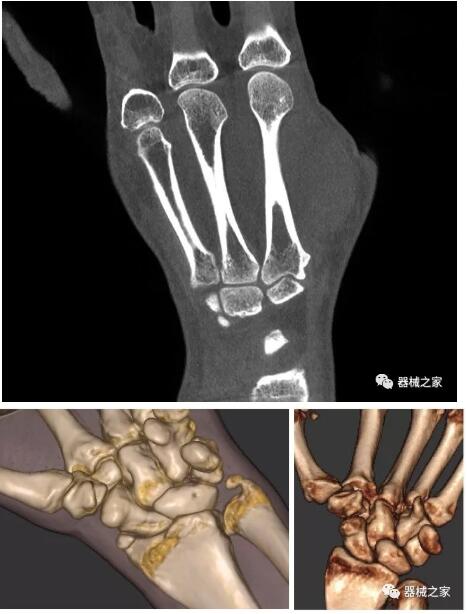

以下是這些“特立獨行”的CT所拍出來的圖像: